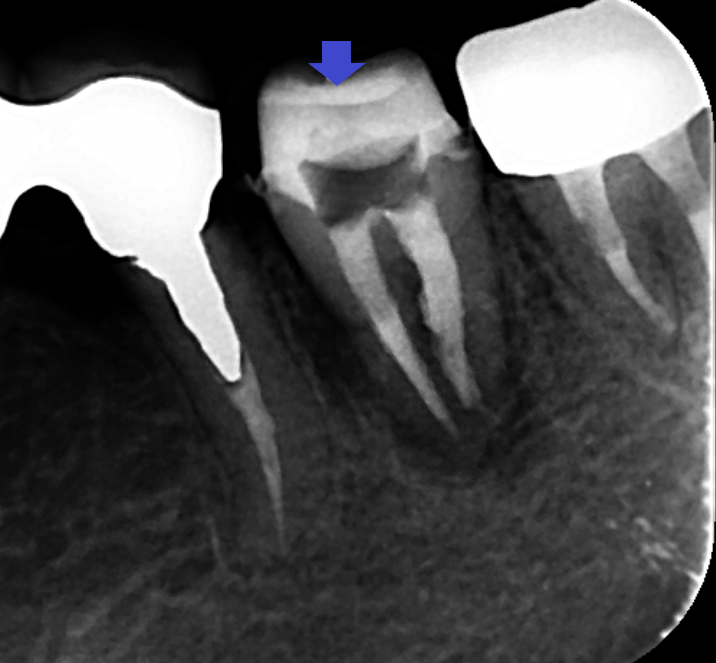

歯根破折を疑わせる影が認められも割れていないことがあります。顕微鏡下で歯根破折は観察されなかったため、精密根管治療を行いました。画像は、根管充填時のレントゲン写真です。